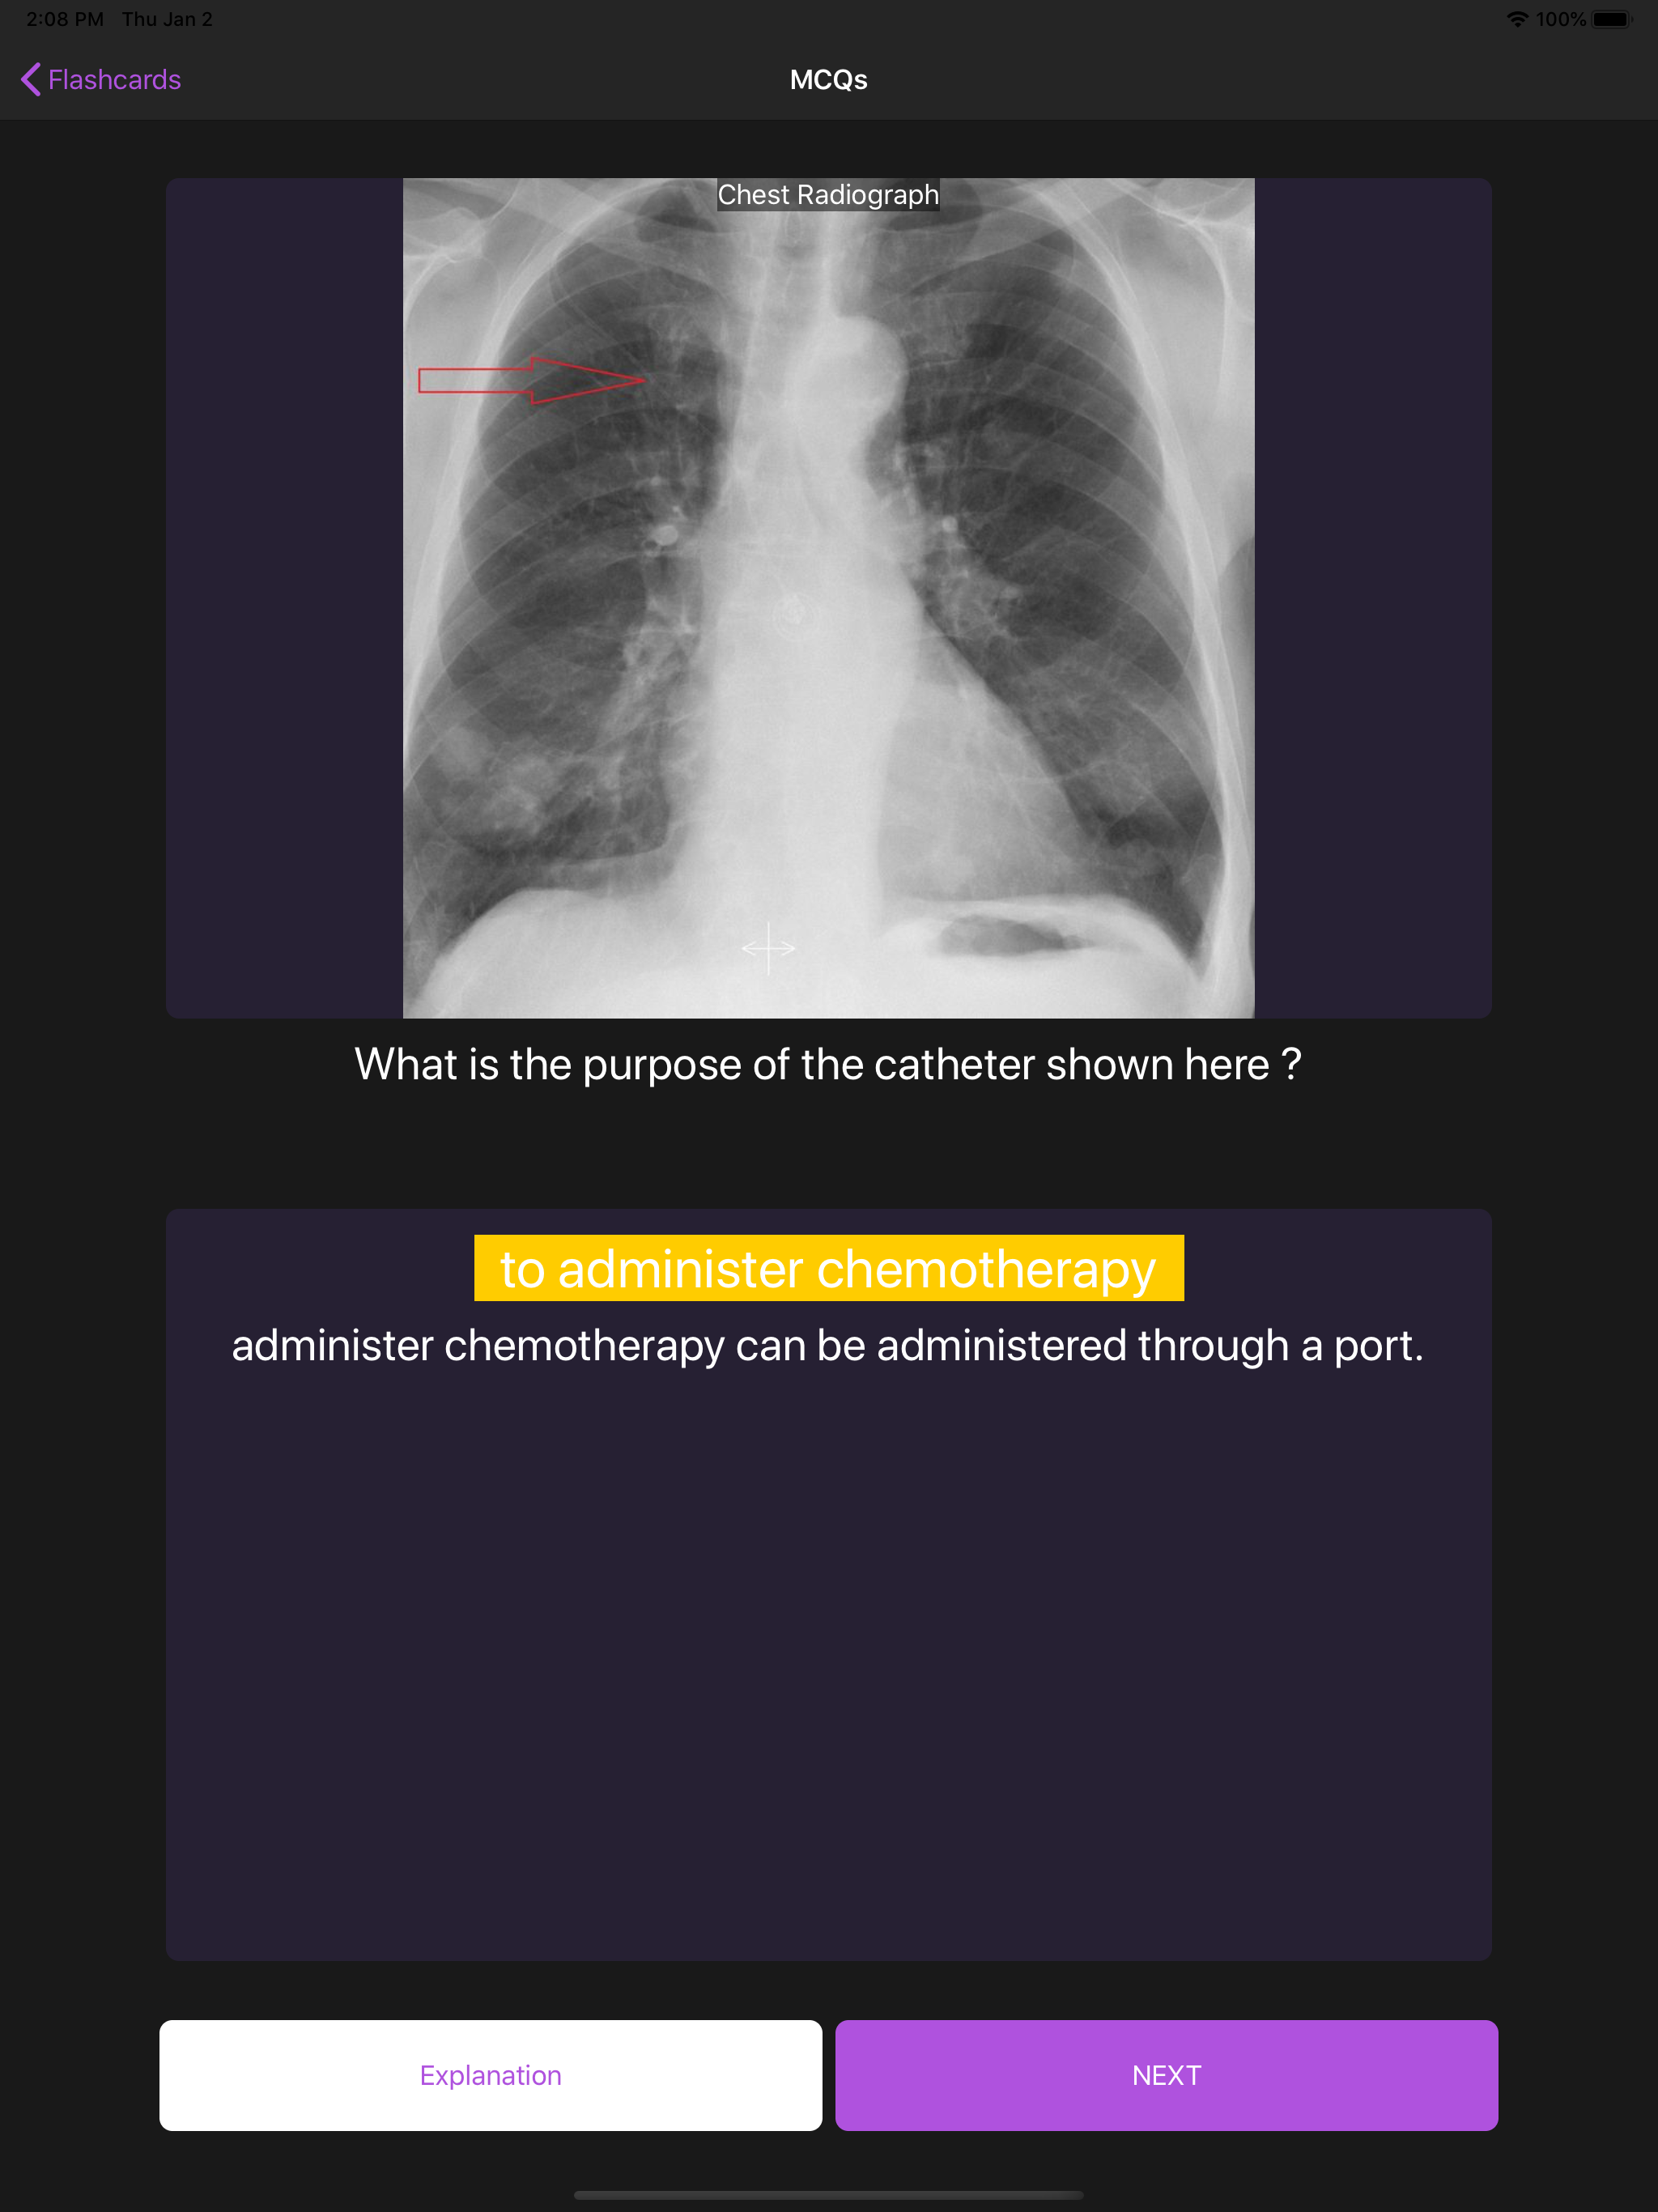

Basic Radiology for medical students is an educational app designed to enhance your radiology knowledge through carefully curated multiple-choice questions (MCQs) with high-quality images, videos, and animations. Practice with a selection of detailed radiology MCQs to build your knowledge. Each randomly presented question comes with comprehensive explanations to deepen your understanding. Access to a selection of questions is available for free. Upgrade to Premium for unlimited access to our complete question bank and maximize your learning potential. Key Features: High-quality radiological images, videos, and animations Detailed explanations for each question Randomized questions for comprehensive learning Note: This application requires an internet connection and user registration. All images are original and professionally labeled. Developed by MCQS, trusted providers of preparation materials for FRCR Part 1 and Part 2 Radiology exams.